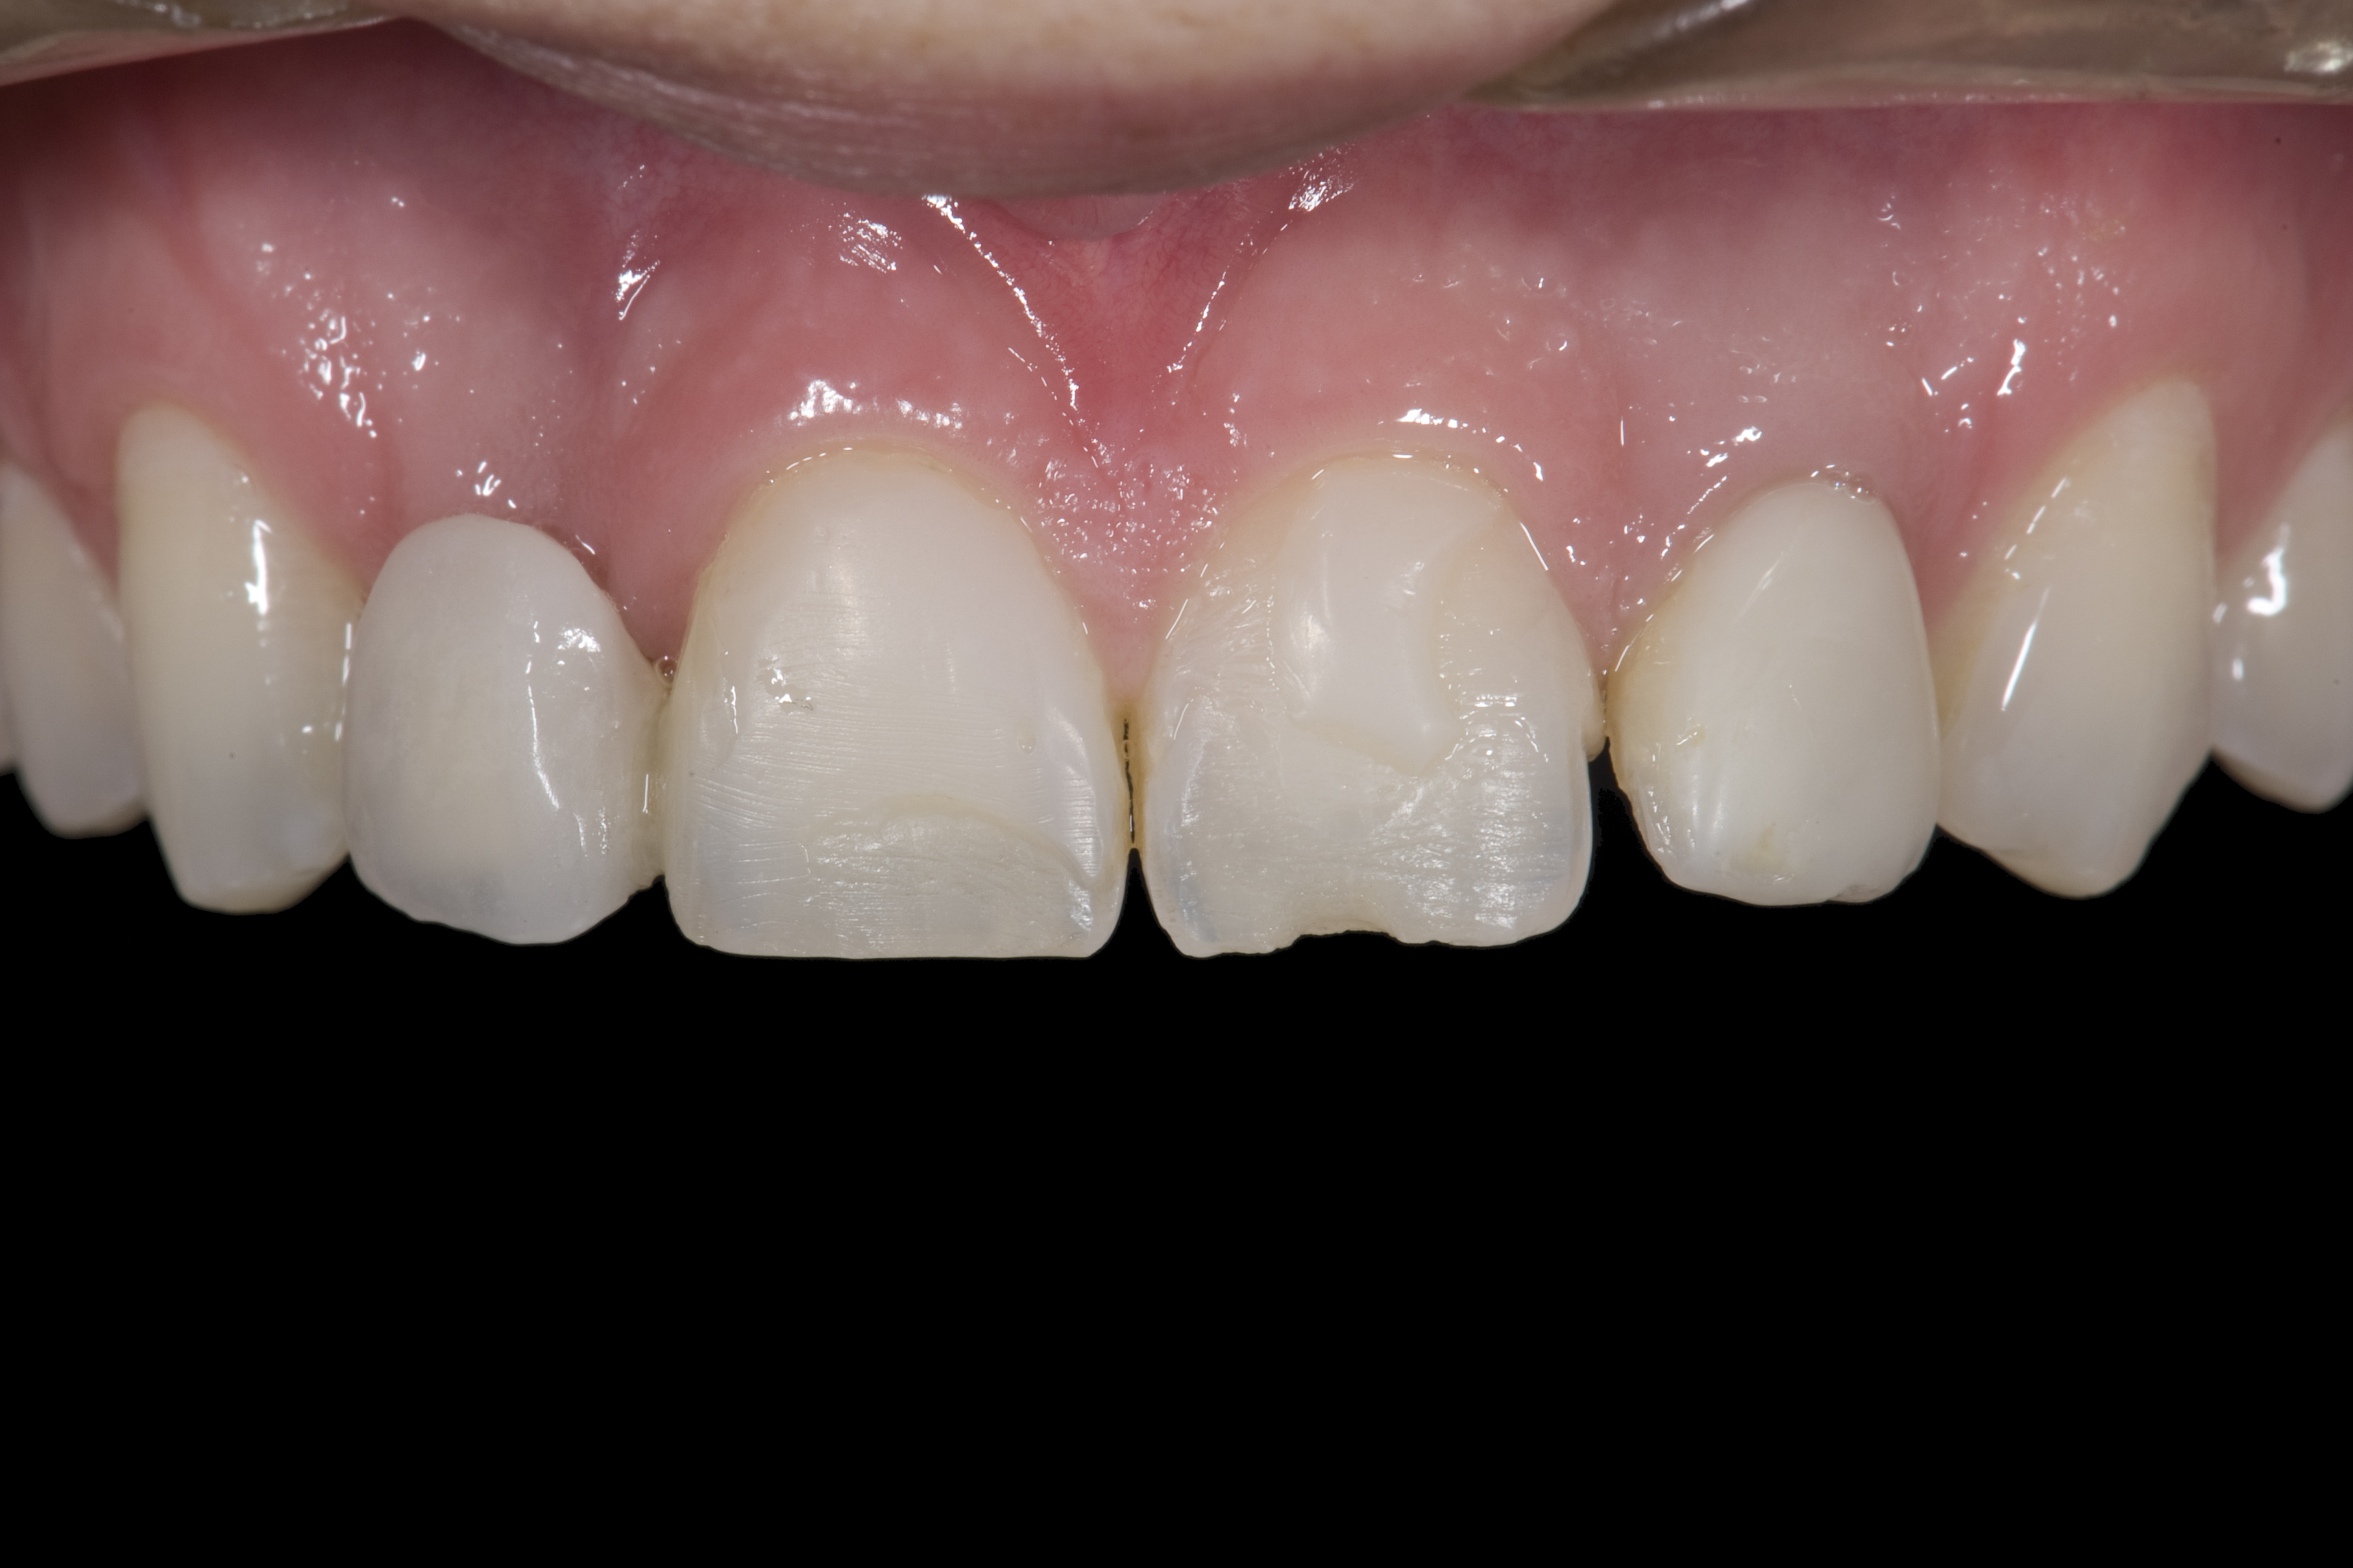

(1.) Initial presentation. Note midline shift to right, missing right lateral incisor, and diminutive left lateral incisor in crossbite.

Figure 1

A 14-year-old patient presented to the office with his mother (Figure 1). His chief complaint involved the large spaces between the teeth created by his missing right maxillary lateral incisor and his small left maxillary lateral incisor. He desired to replace the missing tooth with an implant and create a beautiful smile. Upon examination, he was found to have a class I canine and molar relationship, but because he had a tooth size/arch size discrepancy and space distal to the right central incisor, the remaining incisors had drifted to the right. The left maxillary lateral incisor was peg-shaped and in a cross bite position. Studies have shown a clear association between congenitally missing teeth and reduced tooth size.59-62 Because he was only 14-years-old at the time and could not have implants placed until the cessation of growth (somewhere in the vicinity of 22 years old), he was sent to the orthodontist for alignment of the teeth.16,17 After 2 years of orthodontics, the appliances were removed, and his tooth coloration was improved using carbamide peroxide bleaching (Figure 2). Because some form of provisional needed to be placed until he was finished growing, a double-wing metal resin-bonded bridge was chosen. As discussed earlier, this is the ideal transitional prosthesis for patients that have congenitally missing maxillary lateral incisors. The benefits of this type of prosthesis include its ability to be removed and rebonded during the surgical phase of treatment and its ability to retain the roots in their proper position after orthodontic treatment.16 The final plan for the patient was to increase the width of the central and the maxillary left lateral incisor, utilizing porcelain laminate veneers to achieve the appropriate width/length ratio of 80%. A wax-up was created to idealize tooth size, a putty matrix was made from the wax-up to facilitate bonding of the incisors, and a non-precious, double-wing metal resin-bonded bridge was fabricated for lateral incisor replacement. Once the teeth were bonded to ideal size, the “Maryland Bridge” was fabricated from a polyvinyl arch impression with the newly bonded teeth (Figure 3). The metal frame was cast from a non-precious alloy to allow for fabrication of a very thin frame and to create a better surface for bonding. After sandblasting the internal aspect of the frame with CoJet™ silica (3M ESPE), accomplishing salinization, and executing cementation with a dual-cure resin cement, a fairly good adhesion to the frame was anticipated.29 The enamel surface was etched with phosphoric acid for 30 seconds, the primer (Single Bond Plus, 3M ESPE) was applied to both the internal surface of the sandblasted framework and the etched enamel, and the bridge was cemented with RelyX™ ARC (3M Espe) dual-cured resin cement (Figure 4 and Figure 5).